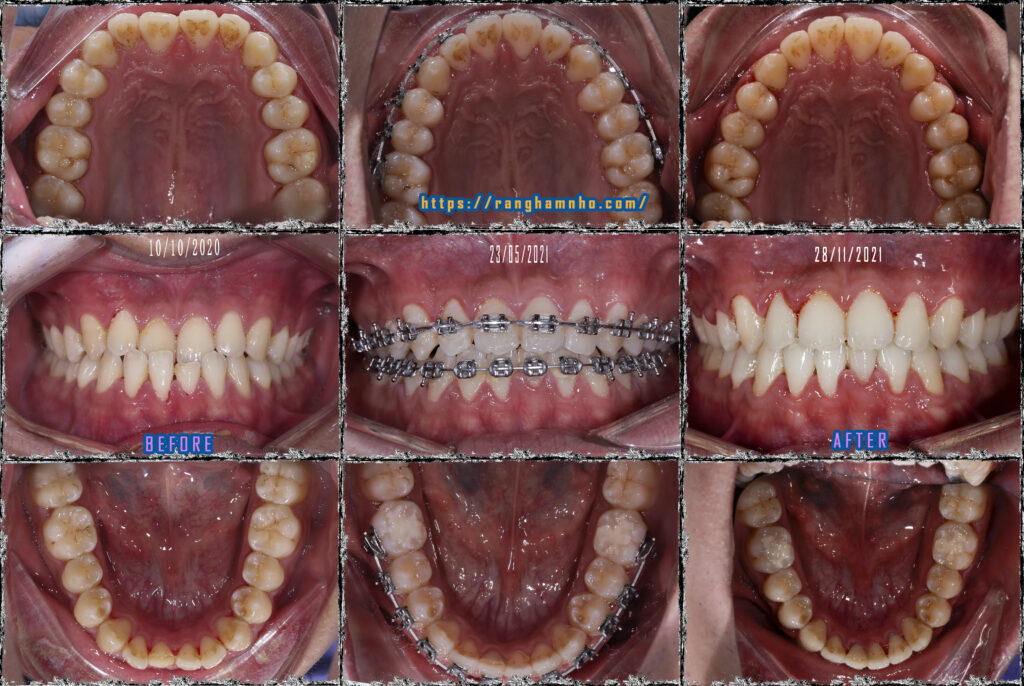

Cũng là khớp cắn ngược nhưng xét về độ khó thì khớp cắn ngược do răng điều trị sẽ đỡ vất vả hơn cắn ngược do xương nhiều. Bệnh nhân nam sinh năm 1998 đến khám niềng với mong muốn cải thiện nụ cười móm.

Bệnh nhân chọn niềng mắc cài truyền thống dây cung thẳng liên tục. Giai đoạn đầu san bằng sắp đều cung răng hai hàm, giai đoạn 2 vượt khớp tạo cắn chùm cắn chìa dương. Giai đoạn cuối tinh chỉnh khớp căn, duy trì và tháo niềng.

Kết quả tháo niềng sau 1.5 năm, thay đổi tích cực trên cả lâm sàng và trên phim xquang.